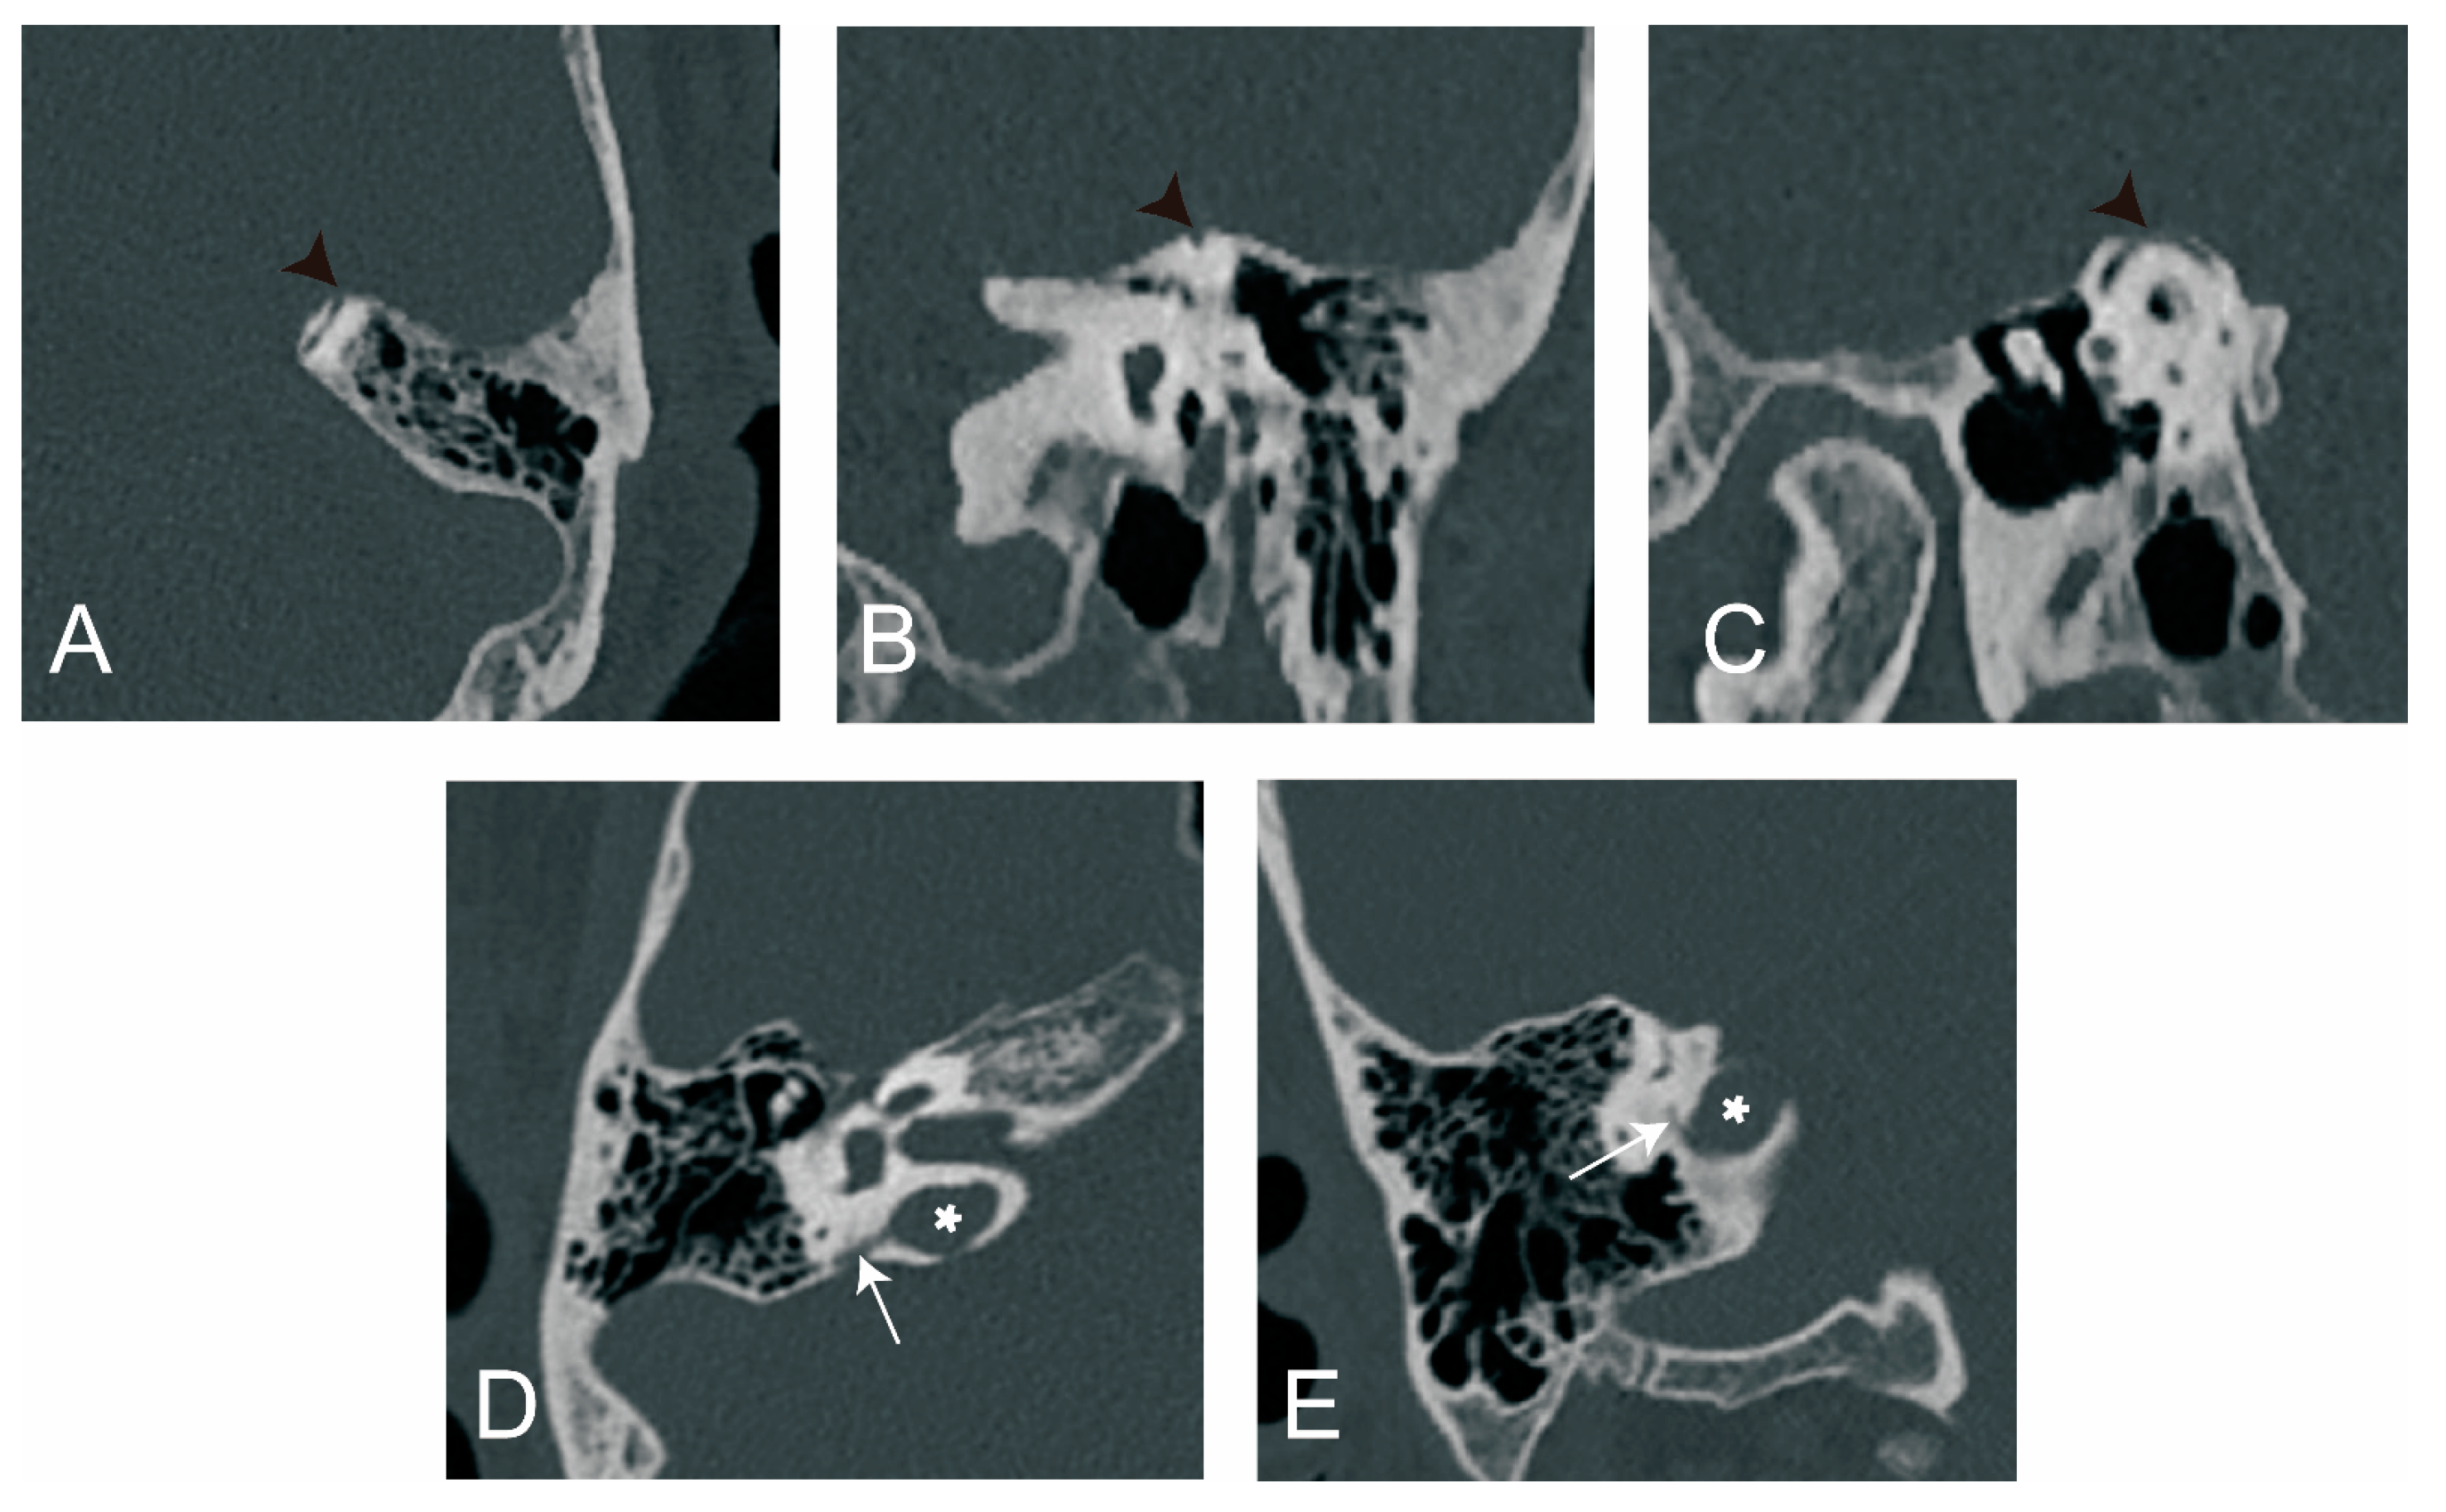

All types of otic capsule dehiscence [23] were evaluated on CT images in at least three different planes, such as axial, coronal, sagittal, Pöschl, and Stenver plane. When a dehiscence was present in at least two consecutive images in all three different planes, it was considered as a true dehiscence (Figure 5).

Figure 5.

Two types of otic capsule dehiscence. Superior semicircular canal dehiscence (SSCD) on (A) axial view, (B) coronal view, and (C) Pöschl view. Vestibular-aqueduct–jugular-bulb-dehiscence (VA-JBD) on (D) the axial view and (E) the coronal view. Black arrowhead: SSCD; white arrow: VA; white asterisk: jugular bulb.

3.2.4. The Relationship between ATVA and Otic Capsule Dehiscence

As shown in Figure 11, otic capsule dehiscence was found in 15/163 (9.2%) of the control ears, 8/125 (6.4%) of the affected ears, and 12/125 (10.4%) of the non-affected ears. No statistical difference in otic capsule dehiscence was found among the above groups ( = 1.322, p = 0.516). Two types of otic capsule dehiscence were found in the present study, i.e., vestibular-aqueduct–jugular-bulb-dehiscence (VA-JBD) and superior semicircular canal dehiscence (SSCD). A combination of VA-JBD and SSCD was detected in one control ear.

The prevalences of VA-JBD in control ears, affected ears, and non-affected ears were 9/163 (5.5%), 4/125 (3.2%), and 6/125 (4.8%), respectively. And the prevalences of SSCD were 7/163 (4.3%), 4/125 (3.2%), and 6/125 (4.8%), respectively. No statistical differences were found in either VA-JBD or SSCD among control ears, affected ears, or non-affected ears (for VA-JBD: = 0.885, p = 0.642; for SSCD: = 0.427, p = 0.808).

In affected ears with ATVA ≤ 120°, 120° < ATVA < 140° and ATVA ≥ 140°, otic capsule dehiscence was detected in 7/77 (9.1%), 1/13 (7.7%), and 0/35 of the ears. No significant difference was detected ( = 3.360, p = 0.145).